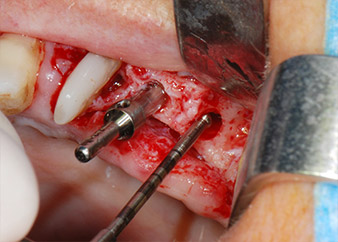

One month later, on the day of surgery, pain and inflammation at tooth 24 were minimal, but mobility of Miller class 2 was still present. After opening the flaps and cleaning the periapical and peri radicular infected tissue, the extent of the bone defect became obvious (Figs. 2 and 3).

At the buccal root, all vestibular and distal bone was missing. Attachment was essentially restricted to the palatal root, underlining the preliminary poor prognosis. Tooth 27 also showed a reduced horizontal attachment and a minimal apical rarefaction (cf. Fig. 1) without clinical symptoms.

total loss of bone and attachment

Fig. 2 and 3: After raising flaps, one month after endodontic revision and initiation of full-mouth periodontal therapy, the buccal root of tooth 24 showed a total loss of bone and attachment.